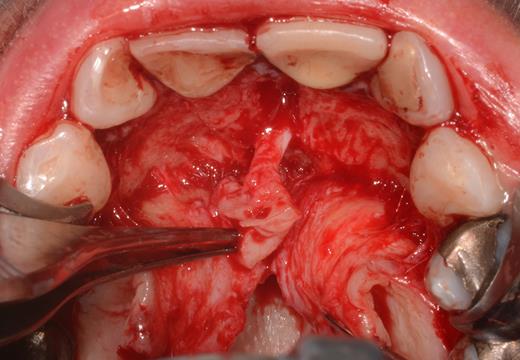

After a sulcular incision on the palatal side from teeth 15 to 25 and an incision in the midline of the palate omitting the incisive papilla and the two orifices of the NPD, two full-thickness mucoperiosteal flaps were raised. Thereafter, the incisive papilla and the whole contents of the incisive canal were enucleated (Figs 4–6). The bony incisive canal was filled with autologous bone harvested from the palatal region (bone scraper) (Fig. 7). A tension-free primary wound closure was achieved by moving the palatal flaps to the midline using single button and interdental vertical mattress sutures (Monocryl 4-0, Ethicon, Johnson & Johnson, USA) (Fig. 8). To avoid wound dehiscence and hematoma, an iodoforme gauze and a palatal plate were applied (Fig. 9). The patient was instructed to rinse three times a day with 0.1% chlorhexidine (formula hospitalis) for 2 weeks postoperatively. Sutures were removed after 14 days.

Situation after removal of the entire soft tissue contents of the incisive canal.